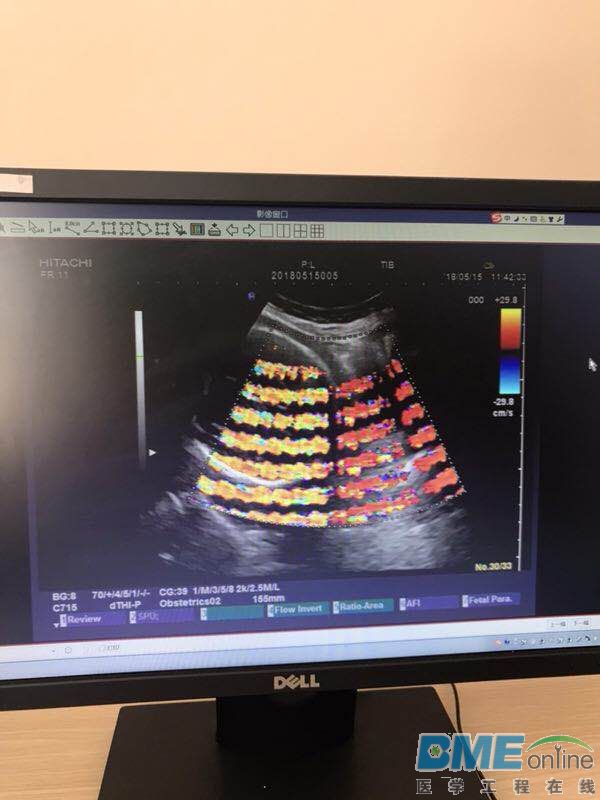

我院的几台B超都有干扰,此干扰时有时无,几乎每天都不定时出现,期间重新做了单独接地、去掉或换了不间断电源,加电源滤波器都没改善。B超室在二楼,有段时间因二楼装修,几台B超移到四楼用就没干扰,搬回来后干扰照旧,救助大家有什么办法消除?

干扰